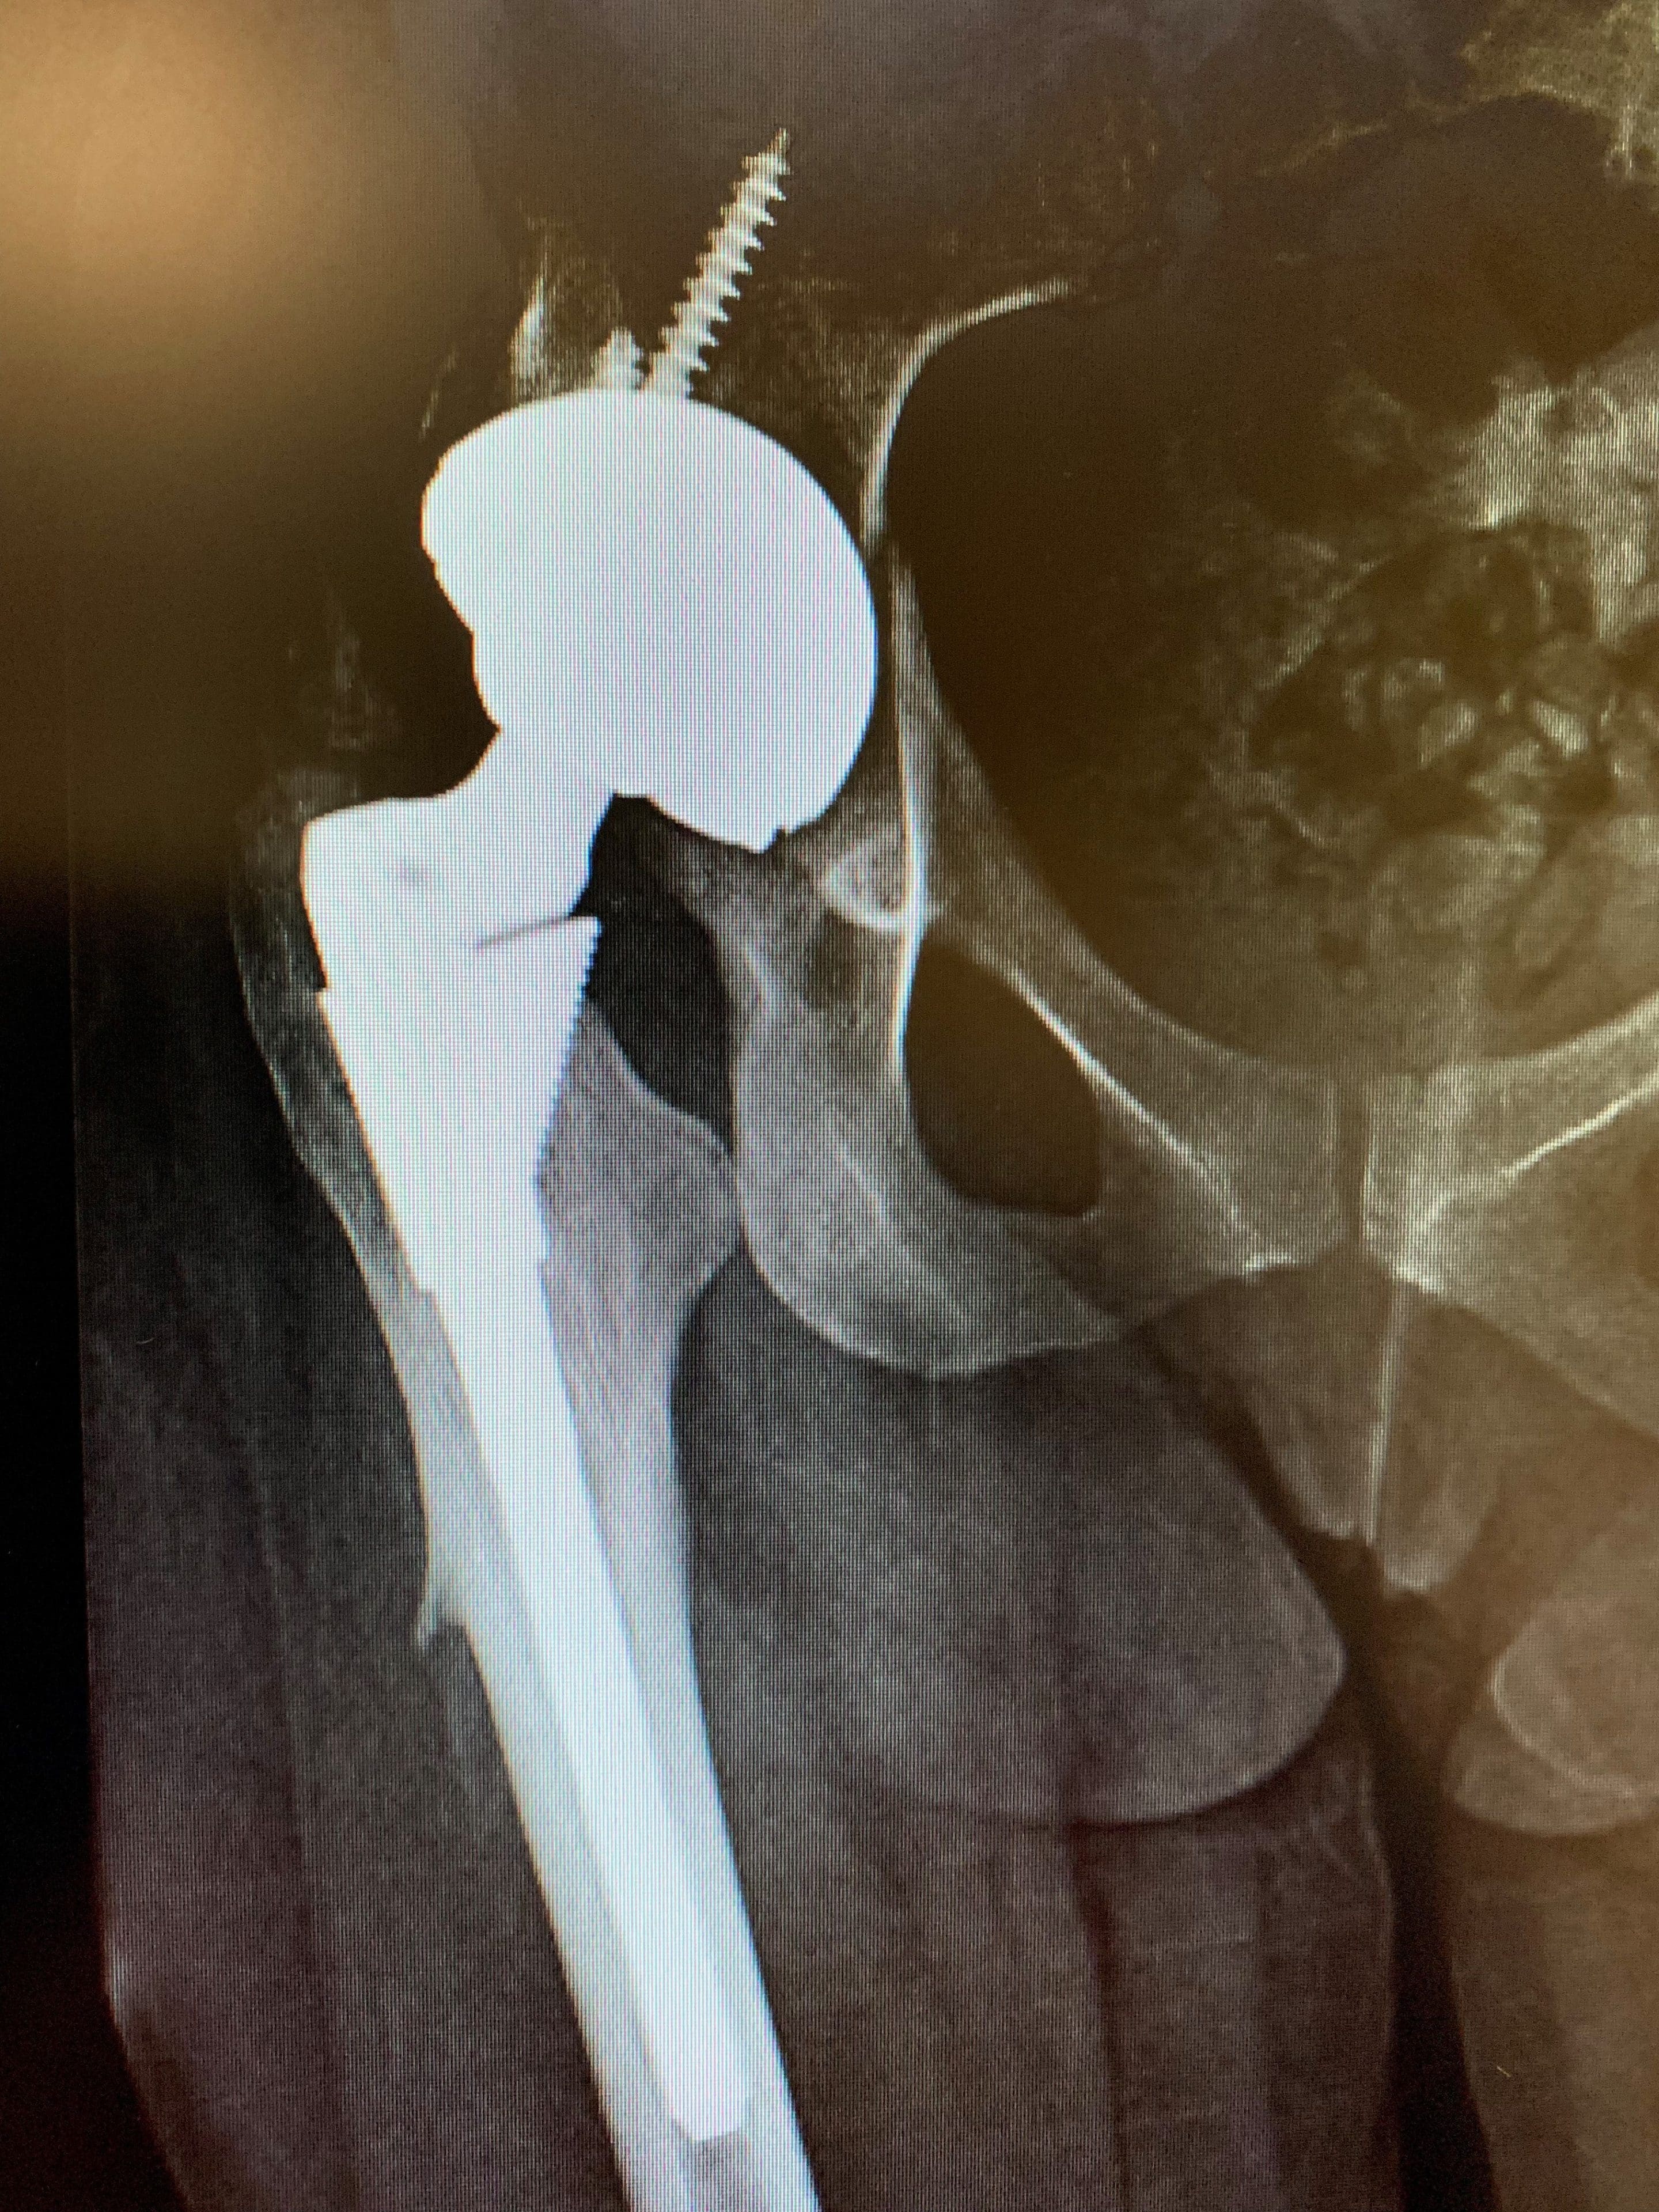

Nuestro plan era intercambiar este componente por una alternativa que facilitara un constructo de doble movilidad, uno que ha demostrado abordar muy bien el problema de la inestabilidad.

Esto se hizo sin incidentes y, tras extensas pruebas de estabilidad, no se observaron dislocaciones. Tras la operación, la señorita EM se sometió a una fisioterapia extensa para fortalecer al máximo a sus secuestradores, otra estrategia para abordar su problema de inestabilidad. Un año después de la operación, todavía se queja de rigidez en la cadera, pero no ha tenido más luxaciones.

Postoperatorio